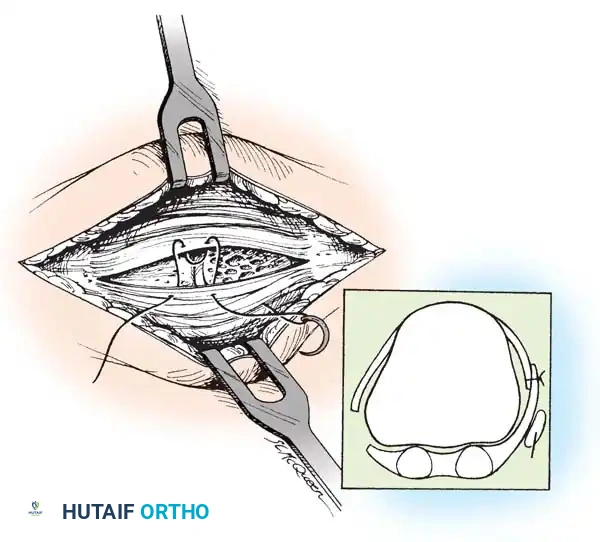

• By sharp dissection, raise the periosteum and the capsule dorsally and plantarward from the base of the proximal phalanx to the proximal edge of the medial eminence (Fig. 78-15). At the proximal end of the medial eminence, avoid releasing the proximal bony attachments of the medial capsule on the metatarsal neck (especially in the dorsal direction) in an attempt to expose the medial eminence. To ensure adequate exposure without disruption of this proximal attachment, a longitudinal capsular incision is suggested.

• Elevate the capsule by sharp dissection dorsalward and plantarward to expose the dorsal aspect of the metatarsal head, the entire medial eminence, and the plantar plate. A periosteal elevator is not recommended because of the possibility that the proximal attachments of the capsule may be released.

L-SHAPED CAPSULAR INCISION

• Alternatively, make the capsular incision in an inverted L shape (Fig. 78-16A).

• Raise the dorsal fl ap deep to the nerve and veins until the accessory slip of the extensor hallucis longus tendon is seen in the proximal portion of the incision where it is easier to identify. The tendon almost always can be located with careful searching. If it is not seen at the dorsomedial aspect of the fi rst metatarsal, however, begin the longitudinal limb of the incision at this slope of the metatarsal from dorsal to medial.

• Begin the incision proximally on the dorsomedial side of the fi rst metatarsal shaft and 2 to 3 mm medial to the accessory slip of the extensor hallucis longus tendon. Carry the incision to the bone at the level of the fi rst metatarsal joint, extending proximally 4 to 6 cm.

• Make the transverse limb of the capsular incision at the level of the joint, stopping 2 to 3 mm from the tibial sesamoid bone; this limb transects the capsular insertion of the abductor hallucis muscle (Fig. 78-16B and C).

Fig. 78-15 Modifi ed McBride procedure. Capsule is opened, and attachment of capsule on metatarsal neck (arrow) is carefully preserved.

• Beginning on the plantar aspect of the incision, remove the capsule from the medial eminence from the inside out. Avoid buttonholing the capsule at the junction of the medial eminence and the metatarsal by directing the small-bladed knife down the slope of the eminence.

• Free the capsule subperiosteally on its dorsomedial surface, and retract it proximally and plantarward (Fig. 78-16D).

• Insert one small Hohmann retractor over the dorsolateral surface of the metatarsal head and another beneath the head at the head and neck junction, while distracting and plantar fl exing the hallux to expose the articular surface of the metatarsal head for evaluation of its condition and orientation. Reduce the hallux congruently on the metatarsal head.

• If the hallux is in more than 15 degrees of valgus after reduction, a distal metatarsal osteotomy is needed.

Fig. 78-16 InvertedL capsulotomy. A, Skin incision. B, Most medial branch of superfi cial peroneal nerve. C, Limits of capsulotomy. D, Capsule raised to expose articular surface of metatarsal head for assessment of orientation on metatarsal head. E, Closure of L -shaped capsulotomy holding fi rst metatarsophalangeal joint reduced.